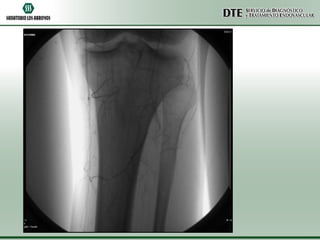

ATPP

•Utilizando una guía hidrofílica de 0.035” se atravesó la obstrucción total crónica y

sobre la misma guía se avanzó un catéter cobra 5F el cuál fue posicionado a nivel del

tronco peroneo.

•Se realizó un test angiográfico a dicho nivel, no comprobándose permeabilidad. No

se visualizaron el llenado de las arterias tibial anterior, tibial posterior ni peronea.

•Se intercambió la guía hidrofílica por una guía de 0.014” y utilizando un catéter de

trombo aspiración Export 6F, se realizó trombo aspiración mecánica a nivel del

segmento ocluido.

•Se logró aspirar gran cantidad de material trombótico fresco, a pesar de lo cuál no

pudo recanalizarse exitosamente la obstrucción total.

•Debido al riesgo de comprometer con microembolias la circulación colateral, se

decidió dar por terminado el procedimiento.

•El control angiográfico final demostró una sensible mejoría a nivel de la circulación

colateral con un llenado más rápido de la arteria pedia y el arco plantar.

ATPP •Utilizando una guíahidrofílica de 0.035” se atravesó la obstrucción total crónica y sobre la misma guía se avanzó un catéter cobra 5F el cuál fue posicionado a nivel del tronco peroneo. •Se realizó un test angiográfico a dicho nivel, no comprobándose permeabilidad. No se visualizaron el llenado de las arterias tibial anterior, tibial posterior ni peronea. •Se intercambió la guía hidrofílica por una guía de 0.014” y utilizando un catéter de trombo aspiración Export 6F, se realizó trombo aspiración mecánica a nivel del segmento ocluido. •Se logró aspirar gran cantidad de material trombótico fresco, a pesar de lo cuál no pudo recanalizarse exitosamente la obstrucción total. •Debido al riesgo de comprometer con microembolias la circulación colateral, se decidió dar por terminado el procedimiento. •El control angiográfico final demostró una sensible mejoría a nivel de la circulación colateral con un llenado más rápido de la arteria pedia y el arco plantar.